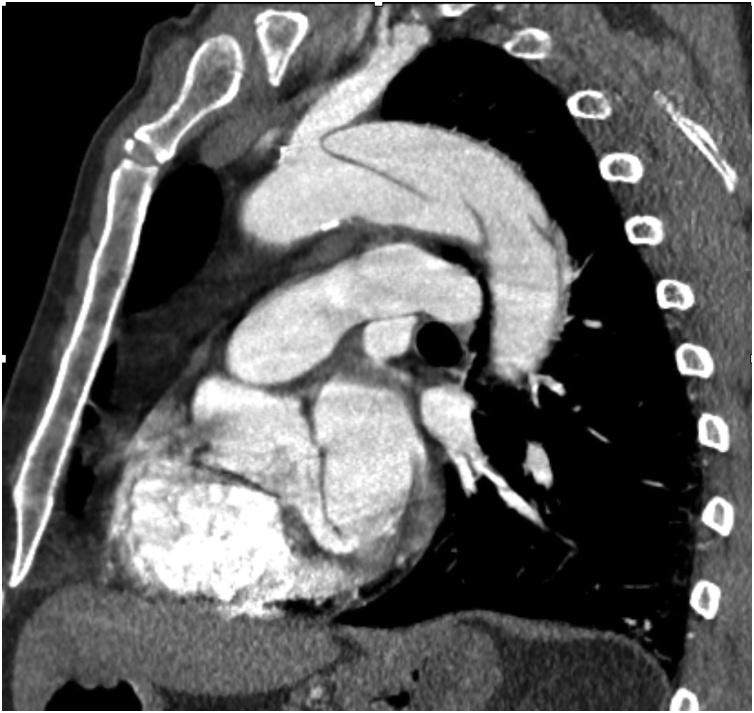

同步症状性急性B型主动脉夹层和大型肾下腹主动脉瘤的同期血管内治疗。技术要点及病例报告。

Simultaneous endovascular treatment of synchronous symptomatic acute type B aortic dissection and large infrarenal aortic aneurysm. Technical tips and case report.

CASE PRESENTATION

We report a complicated case of a symptomatic patient presenting with a type B aortic dissection and false lumen extension into superior mesenteric artery (SMA) with an infrarenal abdominal aortic aneurysm (AAA). Severe back pain and hypertension were the patient's initial complaints. This patient underwent endovascular repair with a thoracic and infrarenal aortic endograft.

我们报告一例复杂病例,一名有症状的患者表现为B型主动脉夹层,假腔延伸至肠系膜上动脉(SMA),同时伴有肾下腹主动脉瘤(AAA)。患者最初的症状是严重背痛和高血压。该患者接受了胸主动脉和肾下腹主动脉腔内修复术。